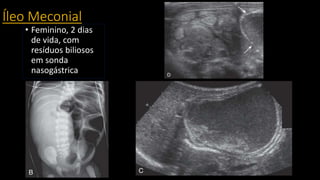

Íleo Meconial

• Feminino, 2 dias

de vida, com

resíduos biliosos

em sonda

nasogástrica